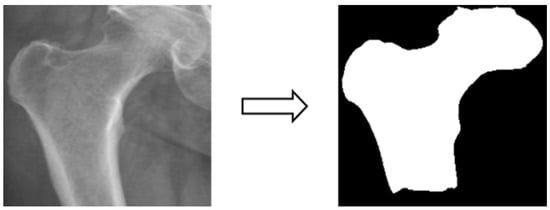

3.3.2. Image Segmentation

In this study, four parts of the image labeled X-ray images were used in image segmentation by feeding them into U-Net and U-Net++ models for training, and the bit depth of the four parts of the image was converted from the original 24 bits to 8 bits before the model training. The reason for choosing to use U-Net and U-Net++ is that their model structure is simpler, they do not need to spend a lot of time filtering out the remaining noise in the medical images, and they are less likely to form overfits for a small number of image datasets. The binary segmentation prediction results obtained after training the models of U-Net and U-Net++ are shown in Figure 3 below.